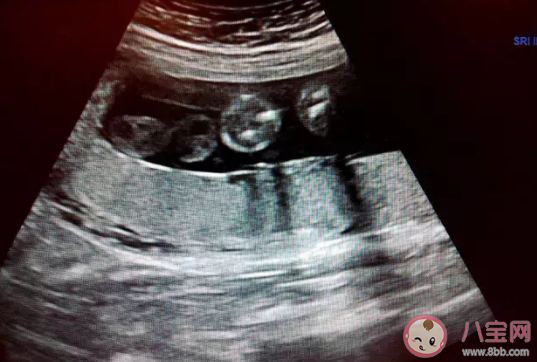

胎盤成熟度對產科醫生來說意義是非常小的,根據胎盤超聲下的提示,把胎盤分為0級、1級(標志胎盤基本成熟)、2級(標志胎盤成熟)和3級(標志胎盤已經衰老),胎盤的成熟度是受到超聲醫生和超聲設備的參數的變化而變化的。